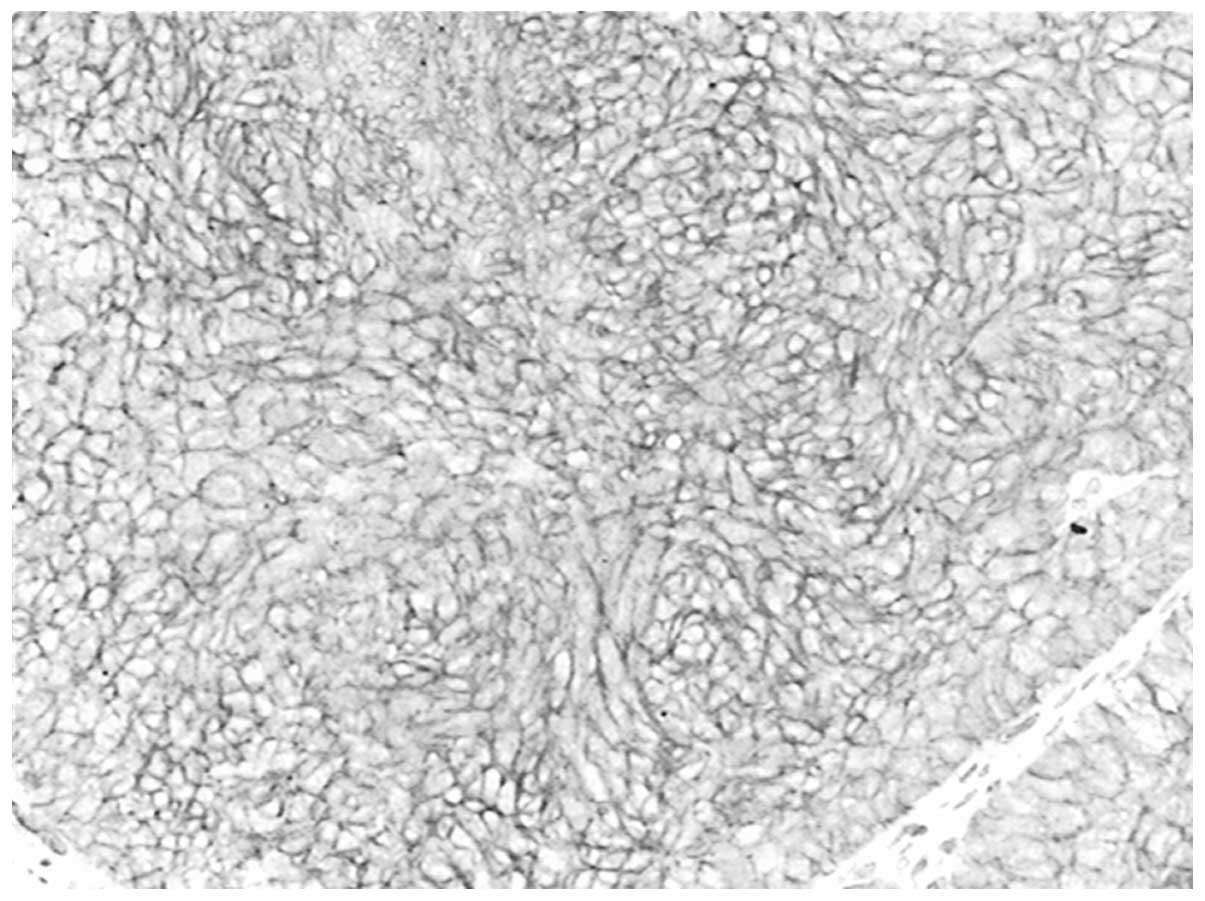

Correlation of CD146 expression and clinicopathological characteristics in esophageal squamous cell carcinoma

CD146, a cell adhesion molecule, is found in normal and tumor tissues. The level of its expression has been found to directly correlate with tumor progression and metastatic potential. The objective of this study was to investigate the expression of CD146 in esophageal squamous cell carcinoma (ESCC) and its correlation with clinicopathological parameters. Tumor specimens were collected from 63 patients with ESCC who underwent complete resection. We analyzed the CD146 expression levels in ESCC by immunohistochemistry. The expression of CD146 was detected and it was observed to correlate with clinicopathological parameters. Sixty‑three cases of normal squamous mucosa were included for comparison. CD146 expression was identified in 46.0% (29/63) of the ESCC samples, and no positive (weak to moderate or moderate to strong) expression was found in the normal squamous epithelium samples (χ2=27.248; P<0.0001). CD146 expression was associated with lymph node metastasis (χ2=5.117; P=0.024) and advanced clinical stage (χ2=4.661; P=0.031). CD146 expression was one of the significant predictors of survival (hazard ratio, 2.838; 95% confidence interval 1.102‑7.305). The overexpression of the CD146 gene was one of the important phenotypes and characteristics in ESCC carcinomatous change. We found that CD146 expression was associated with lymph node metastasis and advanced clinical stage, and was an indicator of poor prognosis in ESCC patients. CD146 may prove to be an important tumor marker for the individualized treatment for ESCC.

View Figures

Figure 1

Figure 2

Figure 3

Figure 4

Figure 5

Figure 6

Figure 7